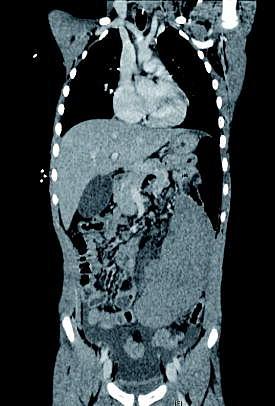

En seksårig dreng blev indlagt med førstegangsmavesmerter, der havde varet i et døgn, opkastninger og subfebrilia. Der blev taget blodprøver, og ved en analyse af disse blev der påvist infektion. Der var mistanke om appendicitis. Ved palpation blev der opdaget en glat, forskydelig udfyldning til venstre for umbilicus. Man havde også mistanke om atypisk infektion, men kunne ikke udelukke leukæmi eller lymfom. En ultralydskanning (US) viste, at der ikke var perfusion af milten. En computertomografi (CT), hvor der forinden var blevet givet intravenøst (i.v.)-kontrastmiddel, viste, at milten var forstørret, og at der var ødematøs milthilum uden kontrast i hilumkarrene. Hounsfieldværdier i milten var 55 mod 85 i leveren. Ved en hurtig gennembladning af CT-billederne sås der en tydelig torsion af miltkrøset, hvorimod appendix var normal. Der var lidt fri væske i fossa rectovesicalis. Drengen blev splenektomeret, og der blev iværksat vanlig vaccinationsprofylakse. Ved kontrolbesøg efter en måned var han rask.

Vandremilt er en medfødt, utilstrækkelig ligamentøs fiksering af milten i den venstre del hypokondriet [1]. En tredjedel af torsionstilfældene ses hos børn [2]. Tilstanden medfører i begyndelsen stase, siden kompromitteret tilløb, og der kan udvikles nekrose. Tilstanden bevirker, at patienten får smerter, der opstår tryk på de omliggende organer, og patienten får kvalme og opkastninger [3].

Klinisk er diagnosen vanskelig. Derfor skal US med farve-Doppler og CT med i.v.-kontrast udføres hurtigst muligt. Husk hurtig gennembladning af CT-billederne.